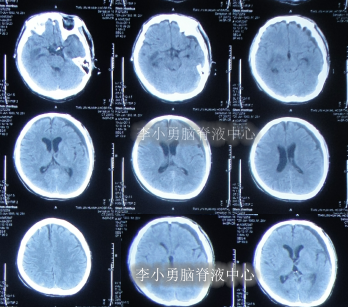

腰大池持续引流2天后即2011年7月1日,疑似有脑脊液鼻漏,查头部CT示未见明显异常(图-6)。

图-6:2011年7月1日头部CT

拔除腰大池引流后2天即2011年7月9日,查头部CT后认为无“异常”(图-7)。

图-7:2011年7月9日头部CT